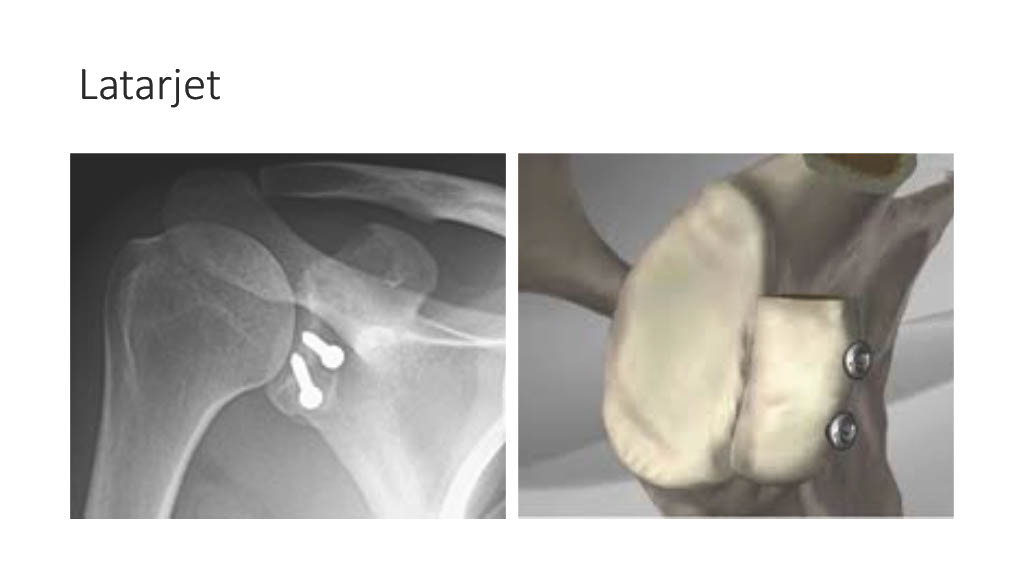

Vogrin, Matjaž, MD, PhD.

Department of Orthopaedics & Sports Medicine Institute, University Medical Centre Maribor, Slovenia

“Surgical treatment of knee injuries in skiing”

Prof. Matjaž Vogrin is an orthopaedic surgeon and specialist in arthroscopic surgery and sports injuries. He is chairman of the Institute of Sports Medicine ” at the Faculty of Medicine in Maribor, Slovenia, and head of the medical subdivision of the Slovenian National Olympic Committee.

He was chief physician of the Slovenian Olympic team at the 2012, 2016, 2021 and 2024 Olympic Games (London, Rio, Tokyo, Paris), official physician of the Slovenian national football team and head of the Slovenian medical team at the 2010 FIFA World Cup in South Africa. He has also been head of the medical team of FC Maribor ( UEFA Champions League and Europa League participants) since 1999. He has been an invited speaker at sports medicine congresses and conferences worldwide.

Surgical treatment of knee injuries in skiing